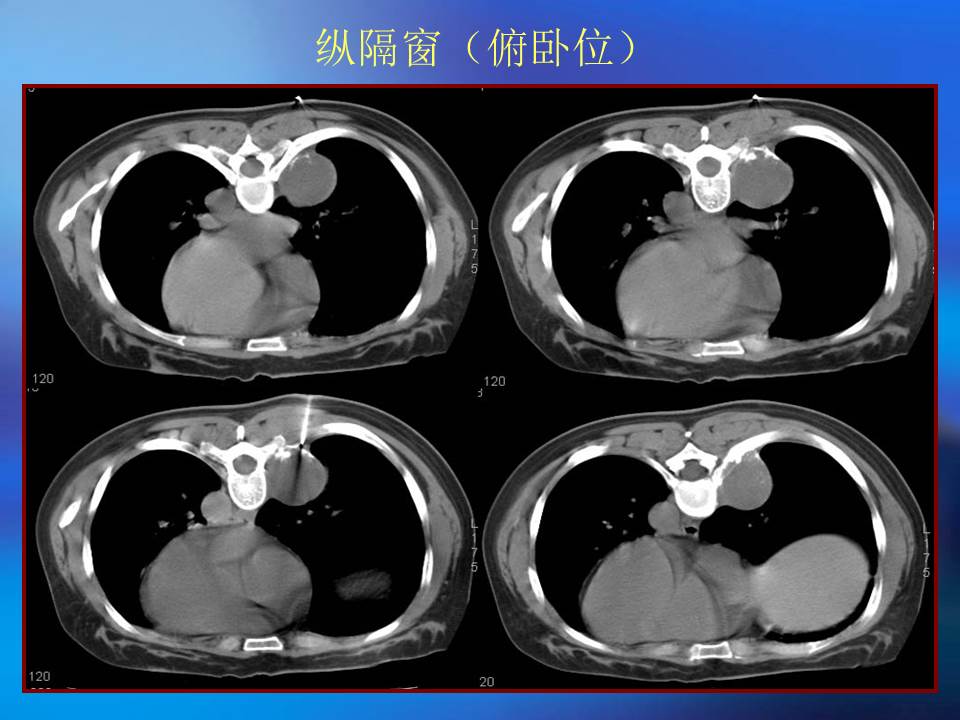

肺良性肿瘤